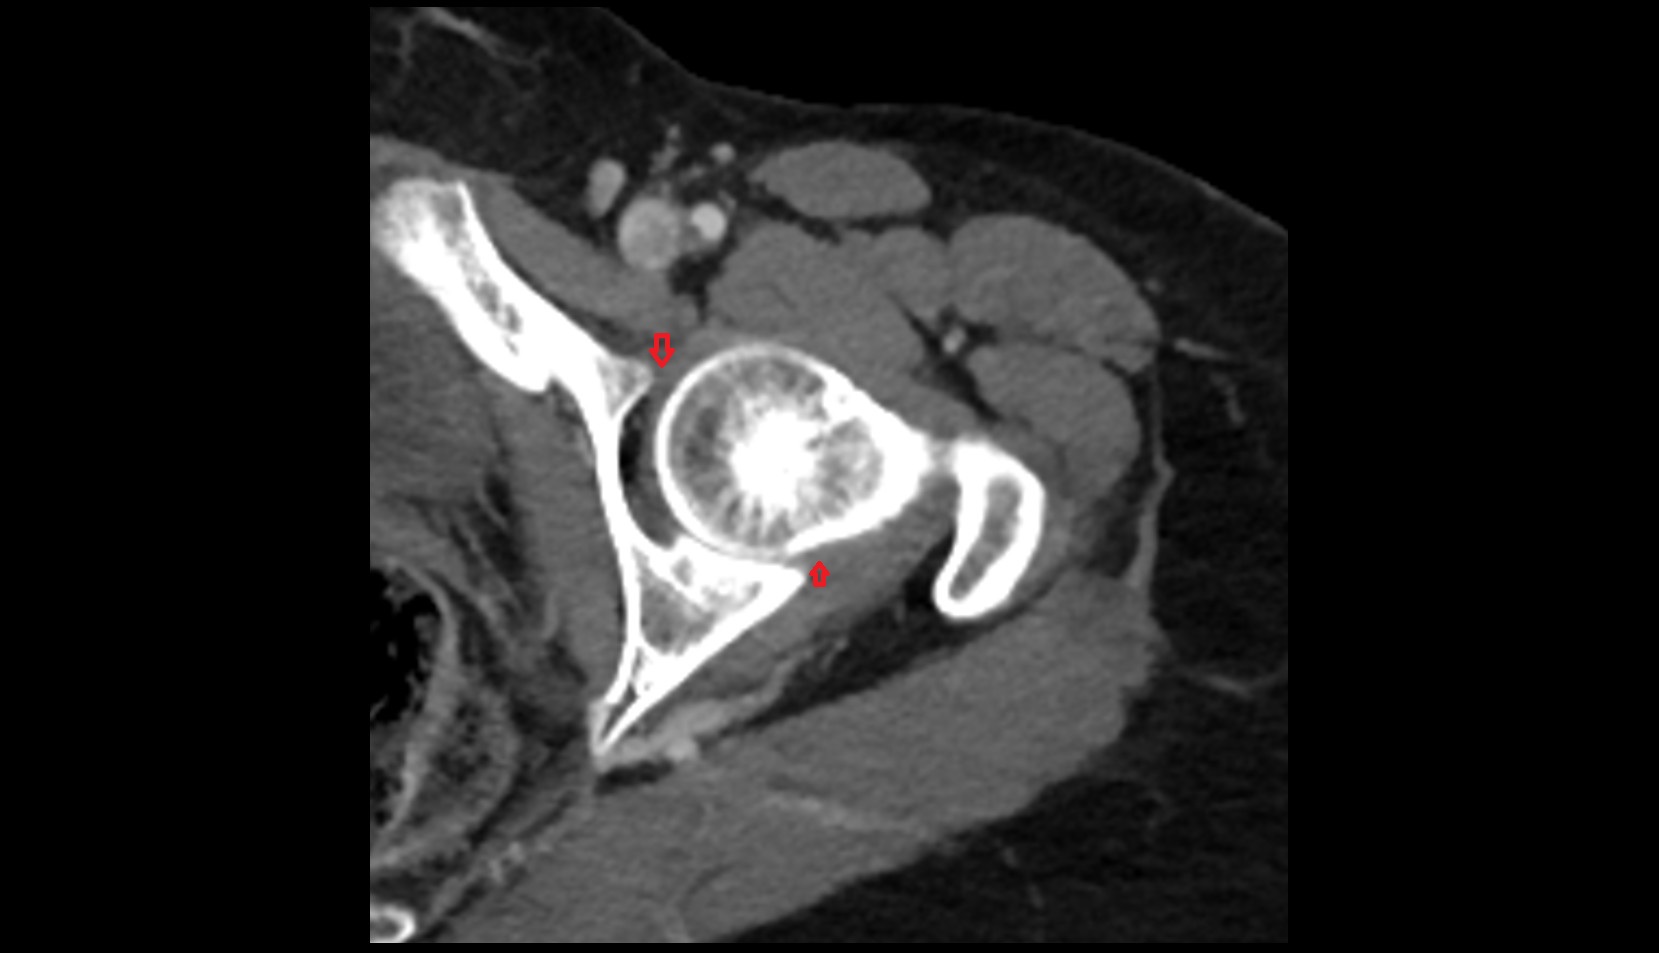

- Head of femur

- Acetabulum

- Hip joint